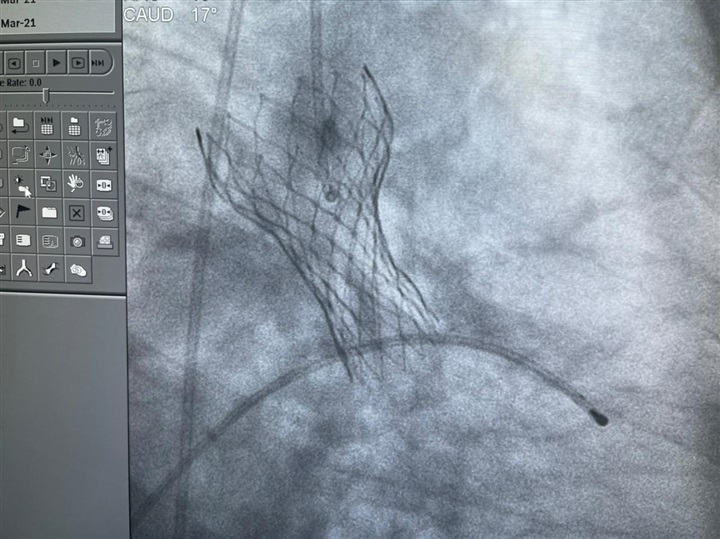

واشارت الهيئة العامة للرعاية الصحية، إلى أن تقنية (التافي) هي أحدث التقنيات المستخدمة لعلاج أمراض القلب، ومن أحدث ما توصل إليه العلم في عمليات استبدال الصمام الأورطي، والتي تعني استبدال الصمام من دون شقّ منطقة الصدر، وذلك عن طريق القسطرة دون اللجوء إلى الجراحات التقليدية كالتدخل الجراحي في جراحات القلب المفتوح.اقرأ أيضًا..

وأضافت أنه تم إجراء عملية استبدال الصمام الأورطي للمريضة عن طريق تقنية التافي؛ حيث كانت تعاني من ضيق شديد بالصمام، إضافة إلى إصابتها بمرض السكري والسمنة المفرطة وارتفاع ضغط الدم، والذي أدى إلى صعوبة التعامل مع الحالة المرضية جراحيًا وعدم اللجوء إلى الجراحات التقليدية واستبدالها بتقنية التافي؛ حفاظًا على حياة المريضة.

واستكملت الهيئة، أن مستشفى النصر التخصصي التابعة لها ببورسعيد أجرت عملية استبدال الصمام الأورطي للمريضة عن طريق تقنية التافي وهي من جراحات القلب المعقدة، بتكلفة مساهمة 300 جنيه فقط لا غير؛ حيث إنها من منتفعي التأمين الصحي الشامل بالمحافظة، وأنه تتجاوز تكلفة إجراء مثل هذه العمليات في مستشفيات القطاع الخاص سواء بمصر أو خارجها الـ500 ألف جنيه.وأكد الدكتور أحمد السبكي، رئيس مجلس إدارة الهيئة العامة للرعاية الصحية، مساعد وزير الصحة والسكان، المشرف العام على مشروع التأمين الصحي الشامل، أن عملية استبدال الصمام الأورطي بالقلب عن طريق تقنية التافي (TAVI) تعد من العمليات فائقة الدقة التي يحتاج إجراؤها إلى خبراء في مجال القسطرة القلبية، مشيدًا بما تحتويه مستشفى النصر التخصصي التابعة للهيئة ببورسعيد من عناصر طبية متميزة وأطقم طبية ماهرة وتقنيات وتجهيزات طبية على أعلى مستوى بوحدة قسطرة القلب في المستشفى، والتي أصبحت تُحاكي أكبر وحدات القلب العالمية بشهادة الخبراء العالميين المتخصصين.